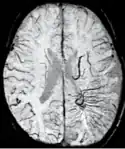

Diffusion weighted imaging offers a powerful means to detect acute stroke. Although it is well known that gradient echo imaging can detect hemorrhage, it is best detected with SWI. In the example shown here, the gradient echo image shows the region of likely cytotoxic edema whereas the SW image shows the likely localization of the stroke and the vascular territory affected (data acquired at 1.5 T).

The bright region in the gradient echo weighted image shows the area affected in this acute stroke example. The arrows in the SWI image may show the tissue at risk that has been affected by the stroke (A, B, C) and the location of the stroke itself (D). The reason that we are able to see the affected vascular territory could be because there is a reduced level of oxygen saturation in this tissue, suggesting that the flow to this region of the brain could be reduced post stroke. Another possible explanation is that there is an increase in local venous blood volume. In either case, this image suggests that the tissue associated with this vascular territory could be tissue at risk. Future stroke research will involve comparisons of perfusion weighted imaging and SWI to learn more about local flow and oxygen saturation.